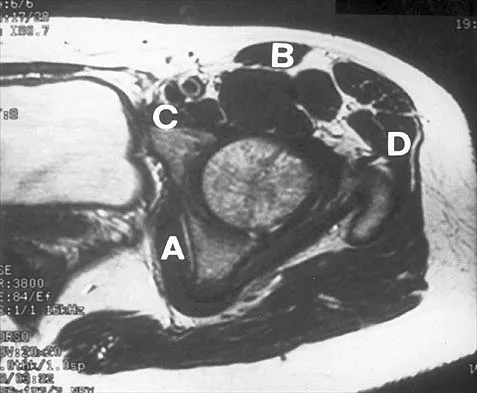

Figure 30 shows an axial cross section of extensor tendon anatomy in zone 7 of the wrist. What letter best depicts the location of the posterior interosseous nerve?

Explanation